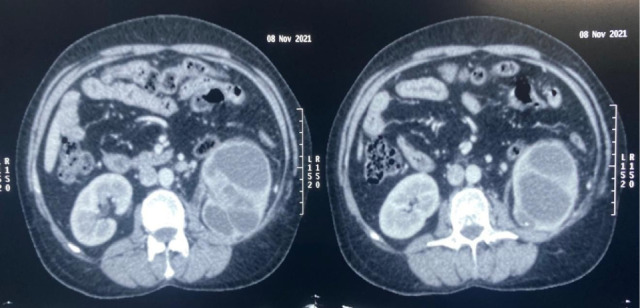

We describe here an atypical case of pyonephrosis which on further evaluation turned out to be a renal cell carcinoma (RCC). The clinical presentation of the patient was that of an infective etiology. However, the renal mass associated with renal vein thrombus and lung metastasis was later diagnosed based on the clinical deterioration of the patient even after insertion of percutaneous nephrostomy. In this case, an underlying renal cancer was probably complicated secondarily leading to pyonephrosis which was the initial presenting manifestation which led to a delay in diagnosis. Pyonephrosis is usually associated with Xanthogranulomatous pyelonephritis. Association of RCC with pyonephrosis is extremely rare and hence seldom reported. Our patient later on underwent radical nephrectomy and the histopathology report was suggestive of RCC. We have described here the clinical manifestations and diagnostic issues of such a case. This case provides evidence that RCC should be kept as one of the differentials in such patients.